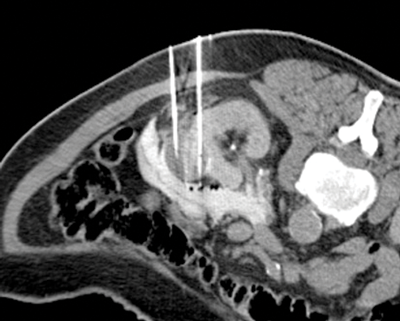

Once the probes are appropriately positioned it may be necessary to protect vulnerable adjacent structures, such as the bowel, pancreas or ureter. The adjunctive techniques most commonly employed to achieve this protection involve the injection of fluid (hydrodissection) or gas (air dissection) to displace at risk structures (Figure 3).

Figure 3: Peri-treatment image depicting cryoprobes within the iceball

and a protective layer of contrast tinted hydrodissection.

In addition the tumour can be manually levered away from the ureter once the tumour has frozen to the probes (commonly termed a ‘stickshift’ or ‘stickfreeze’). Once the probes are positioned our standard double freeze-thaw treatment cycle consists of a 10-minute freeze, 8-minute thaw, and a second 10-minute freeze. The evolving ice ball is visible on CT and imaged during the treatment cycle where it should be seen to consume the target tumour with three-dimensional treatment margins of at least 5mm. Critically, the radiologist has direct control of the power of each probe allowing manipulation of the size and morphology of the ablation zone as it forms.